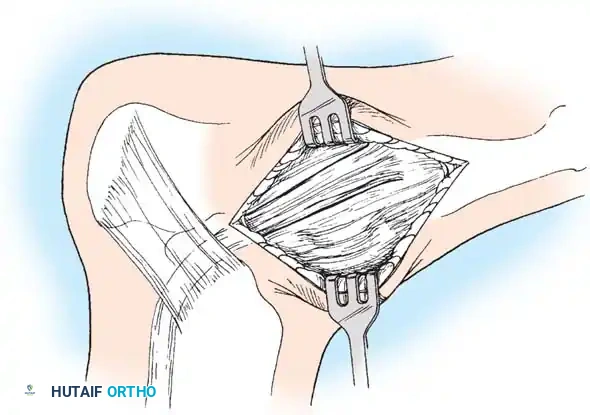

🔪 Surgical Technique 79-6: The Kidner Procedure

1. Incision and Exposure

-

Incision: Begin the skin incision 1 to 1.5 cm inferior and distal to the tip of the medial malleolus. Arch the incision slightly dorsalward, peaking directly over the medial prominence of the accessory navicular, and slope it distally to the base of the first metatarsal.

-

Dissection: Carefully dissect through the subcutaneous tissues. Identify and ligate the plantar communicating branches of the saphenous venous system. Protect the terminal branches of the saphenous nerve.

-

Tendon Identification: Identify the posterior tibial tendon as it approaches the accessory navicular.

-

Tendon Exposure: Identify the dorsal and plantar margins of the PTT approximately 2 cm proximal to the accessory navicular. Expose the tendon distally, ending at the bone.

Surgical Warning: It is imperative to expose the entire tendon without disturbing the portion extending plantarward toward its multiple insertions on the cuneiforms and metatarsal bases. Preserving these plantar slips maintains the structural integrity of the midfoot.